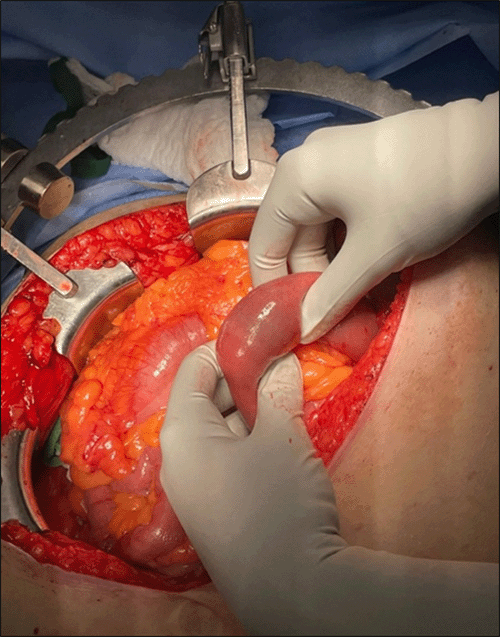

Following consultation with general surgery for gastric outlet obstruction, possibly due to Bouveret syndrome, the patient consented to an exploratory laparotomy with potential bowel resection and open cholecystectomy. Surgical intervention proceeded within 24 hours. While no stone was initially palpable in the proximal small bowel, further exploration revealed a single palpable stone lodged within the jejunum. A 2 cm longitudinal enterotomy was created using electrocautery to access the stone, which was then successfully delivered from the bowel lumen (Figure 3). The enterotomy was closed in an interrupted fashion with 3-0 silk sutures. Additionally, a falciform flap was fashioned and positioned in the right upper quadrant near a visualized cholecystoduodenal fistula. The patient tolerated the procedure well, was extubated in the operating room, and taken to the postanesthesia care unit (PACU) in excellent condition. Her postoperative recovery was uneventful, and she was discharged home four days after the procedure.

Figure 4. Gallstone in the Jejunum. Published with Permission

B) Surgical retrieval of the gallstone via enterolithotomy.